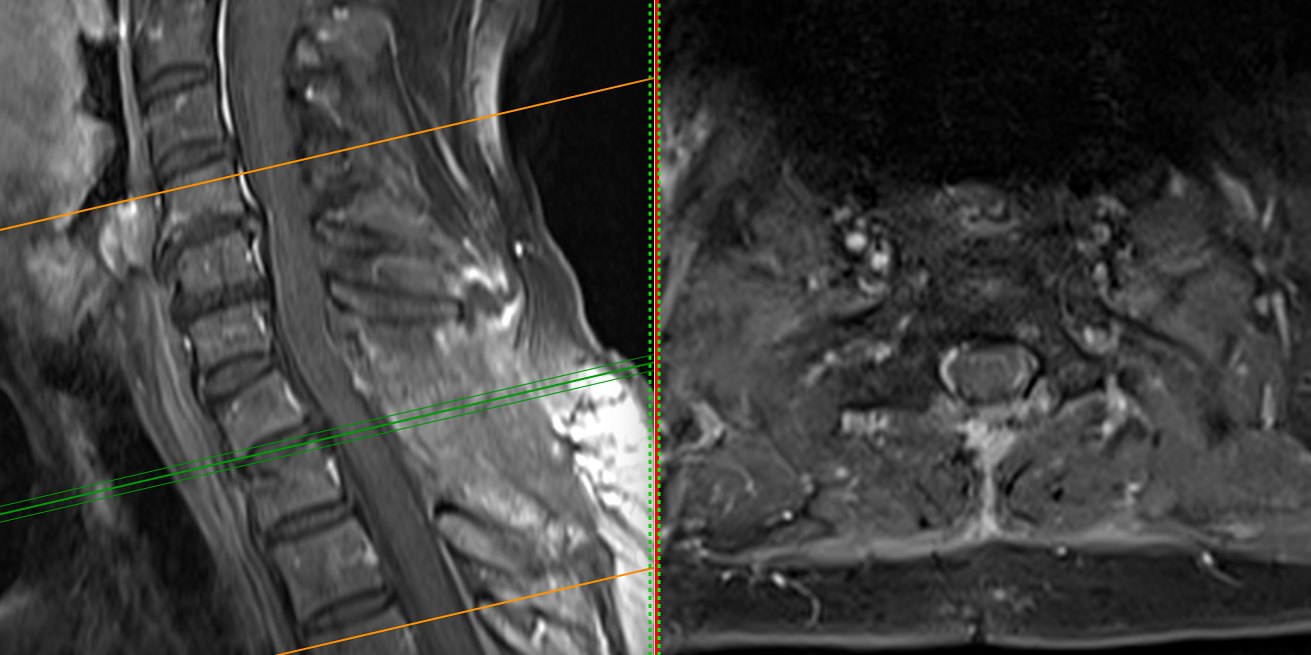

Investigația RMN spinal a evidențiat o formațiune intradurală extramedulară situată la nivel C7–T1, pe partea stângă.

Tumora prezenta caracteristici imagistice sugestive pentru un meningiom: leziune bine delimitată, cu captare omogenă de contrast, cu inserție pe meninge și efect de masă asupra măduvei.

Deși dimensiunea nu era foarte mare, localizarea era critică. La acest nivel, fibrele nervoase care controlează mișcările membrului superior sunt organizate compact, iar orice compresiune — chiar moderată — poate duce la deficit motor progresiv.

Măduva apărea deviată și comprimată, cu dispariția spațiului lichidian din jur — semn clar că structurile nervoase nu mai aveau spațiul necesar funcționării normale.

RMN-ul de control postoperator a evidențiat rezecția completă a formațiunii tumorale.

Măduva apare decomprimată, reexpansionată, cu refacerea spațiului lichidian perimedular — un indicator imagistic esențial al succesului chirurgical.